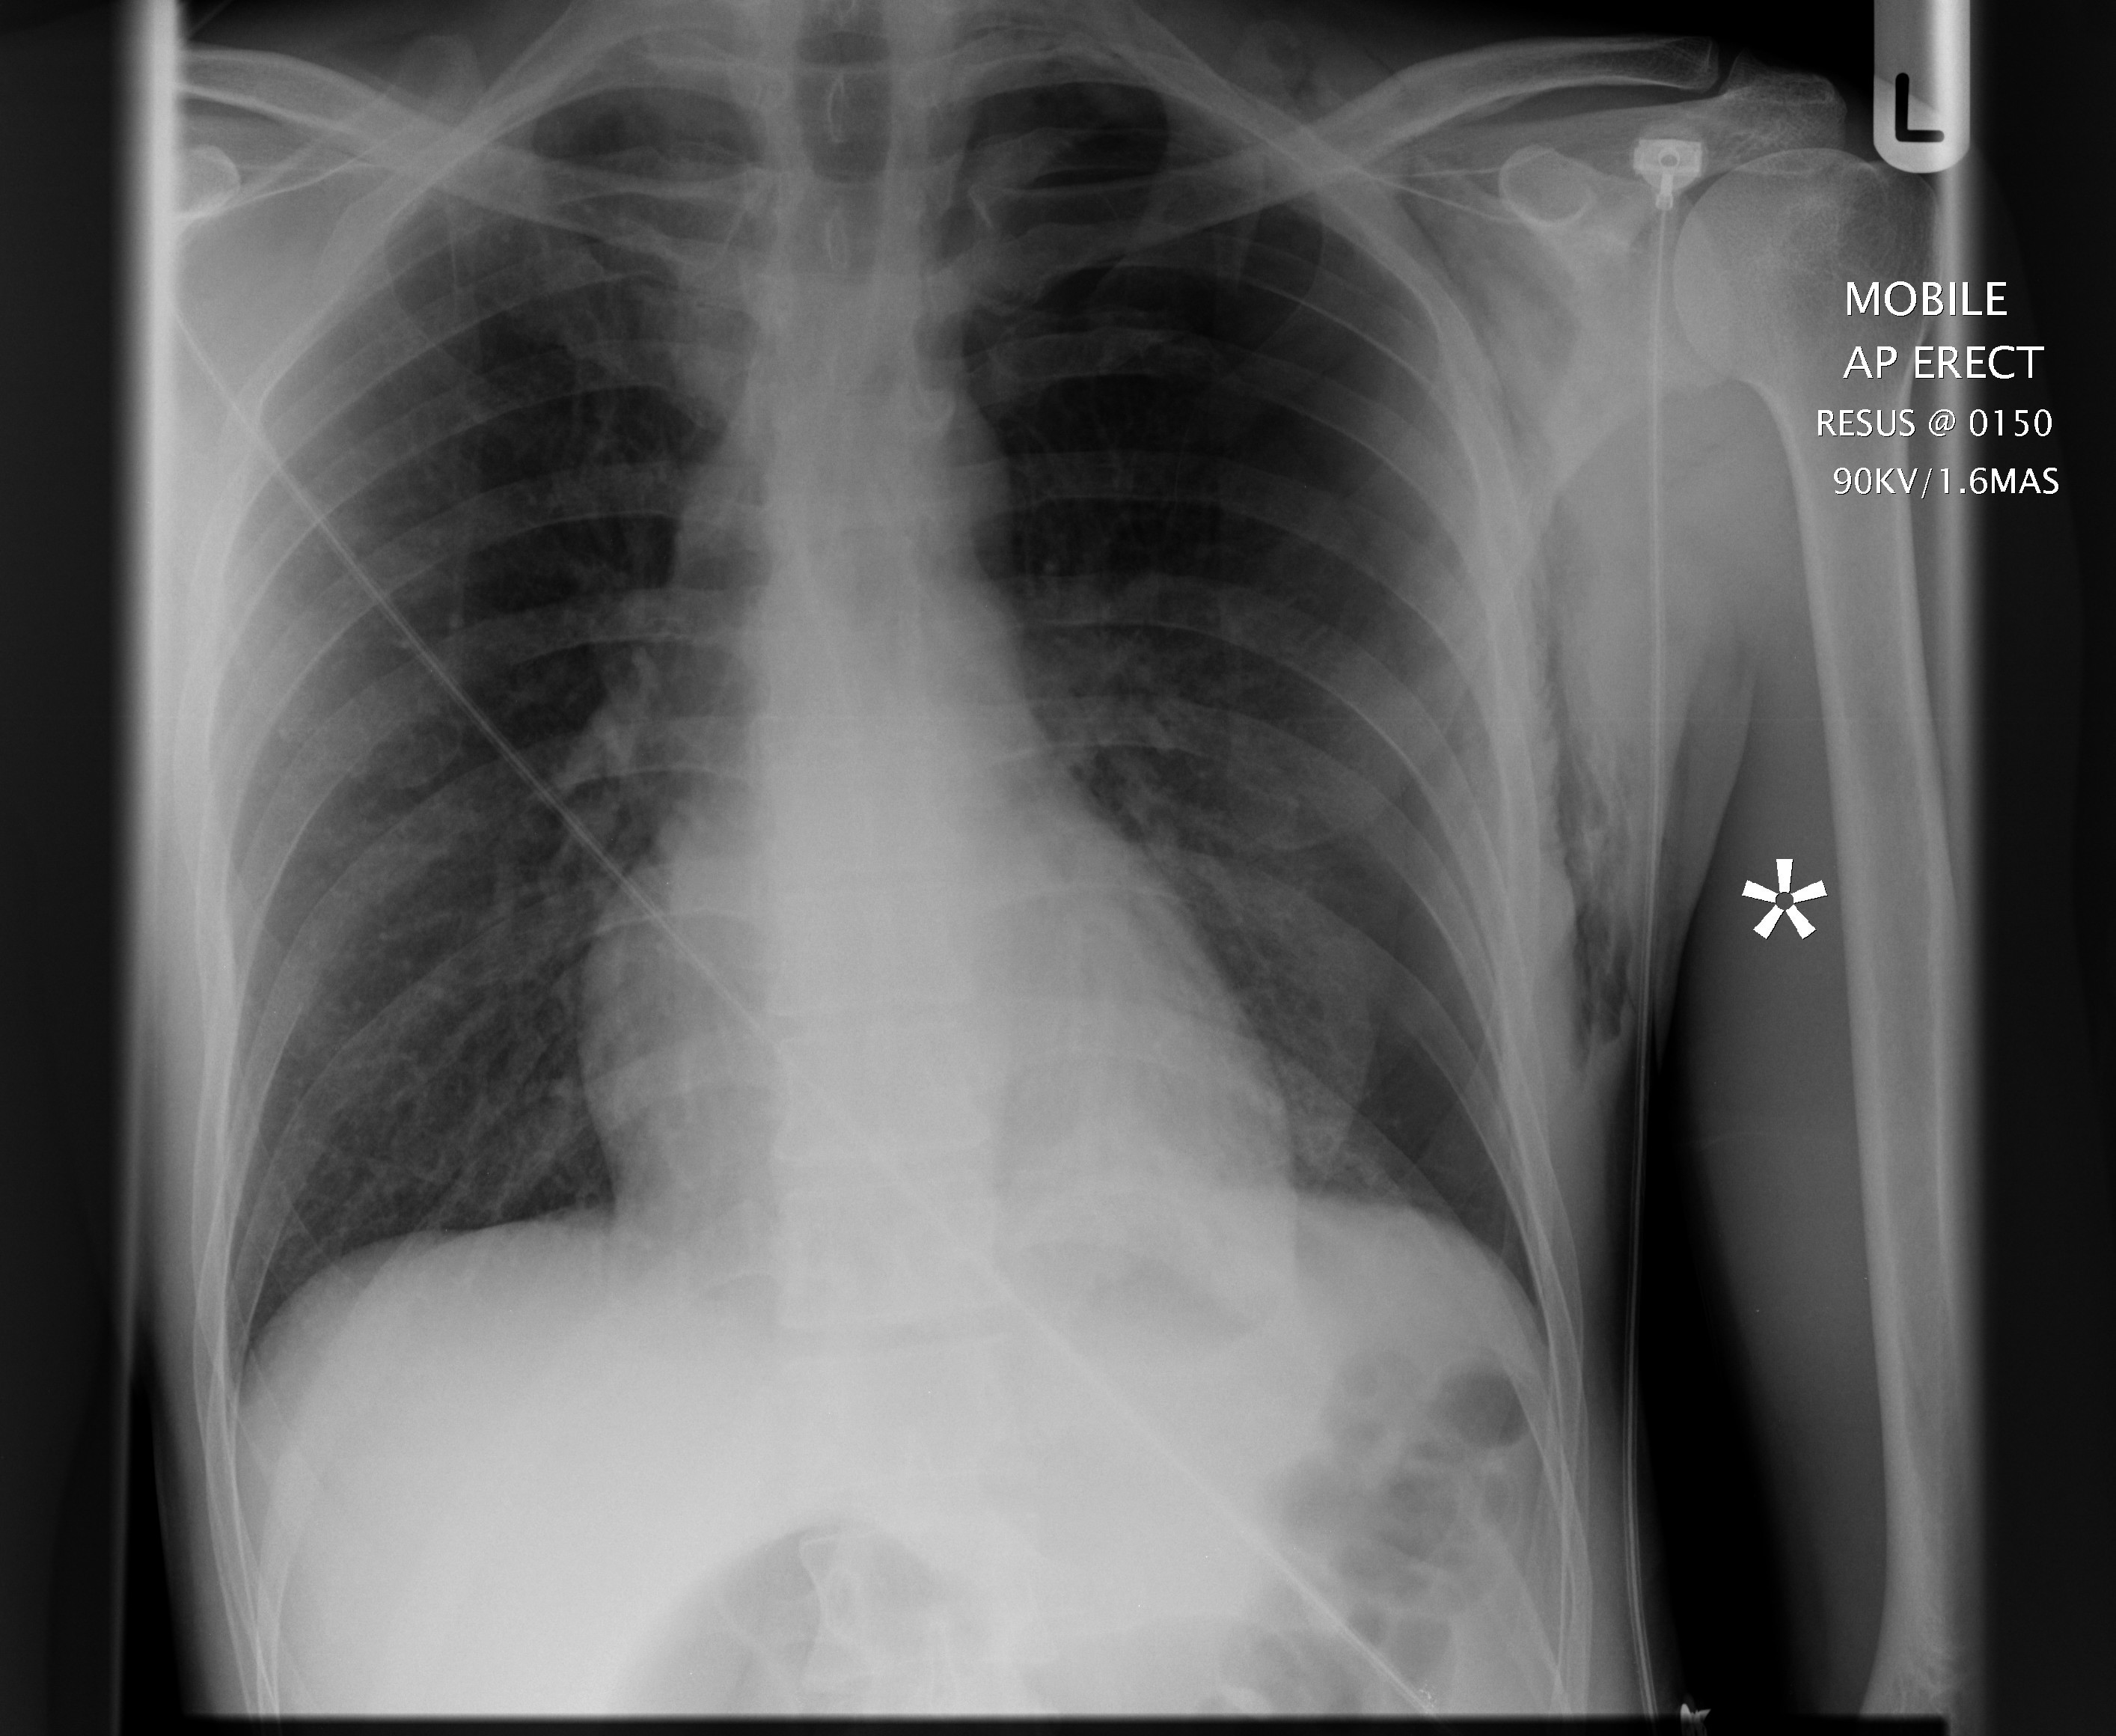

How To Identify Pneumothorax On Cxr . A pneumothorax is a collection of air outside the lung but within the pleural cavity. It occurs when air accumulates between the parietal and visceral pleurae inside the. A visceral pleural line is seen without distal lung markings. It is classified as spontaneous (not caused by. Pneumothorax, the presence of air within the pleural space, is considered to be one of the most common forms of thoracic disease. The radiographic diagnosis of pneumothorax is usually straightforward (fig 1). **note, this video is for. In this video, you'll learn how to identify when radiological pleura is abnormal and the key signs to look out for when trying to. Learn some strategies on how to identify pneumothoraces on xray and ct, including icu xrays.

In this video, you'll learn how to identify when radiological pleura is abnormal and the key signs to look out for when trying to. A pneumothorax is a collection of air outside the lung but within the pleural cavity. A visceral pleural line is seen without distal lung markings. The radiographic diagnosis of pneumothorax is usually straightforward (fig 1). Learn some strategies on how to identify pneumothoraces on xray and ct, including icu xrays. It occurs when air accumulates between the parietal and visceral pleurae inside the. **note, this video is for. Pneumothorax, the presence of air within the pleural space, is considered to be one of the most common forms of thoracic disease. It is classified as spontaneous (not caused by.